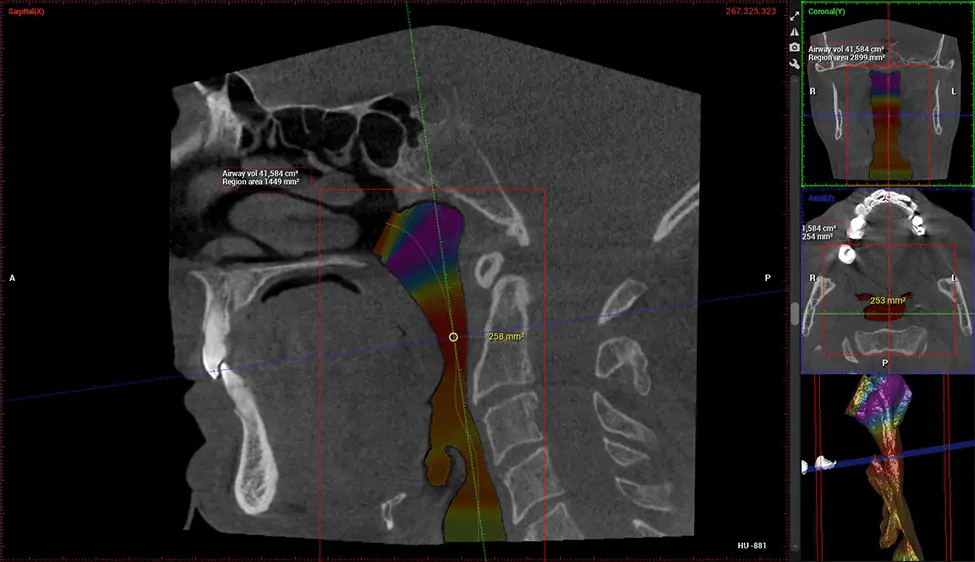

Otorrinolaringólogo Diagnóstico de la apnea obstructiva del sueño (AOS) y evaluación de la anatomía de los senos paranasales y la cavidad nasal. Visualiza toda la vía aérea faríngea para medir el volumen, localizar constricciones y planificar una cirugía correctiva si es necesario.

Especialista en Medicina Dental del Sueño

Detección y tratamiento de pacientes con riesgo de AOS.

Proporciona imágenes 3D detalladas para el análisis de las vías respiratorias, lo que ayuda a crear y ajustar aparatos bucales y facilita derivaciones efectivas a médicos.